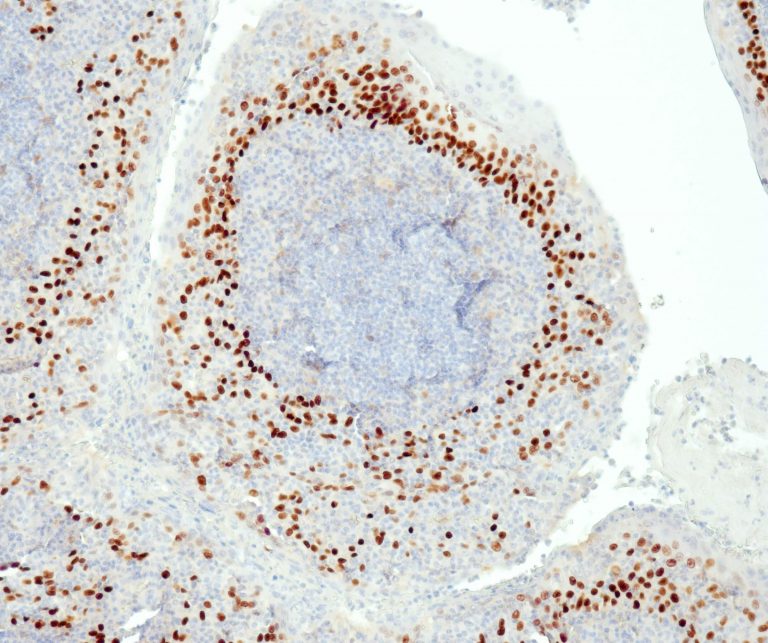

Vascular Pathology

Gastrointestinal (GI) Pathology

General Marker

Breast Pathology

Endocrine Pathology

Gynecological Pathology

Neuropathology

Infection Markers

Lung Pathology

Urinary Tract Pathology

Transplantation Pathology

Soft Tissue Pathology

Hematopathology